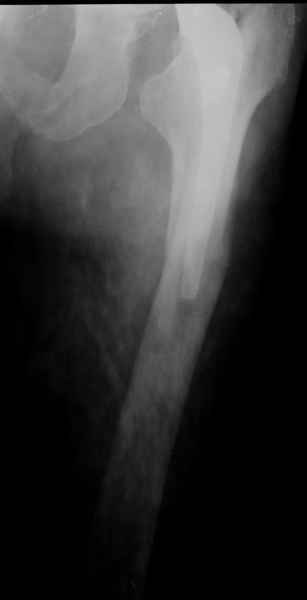

Произведено закрытое удлинение ножки эндопротеза с помощью ретроградного интрамедуллярного стержня. Продолжительность операции 3 часа. Два из них закрытое восстановление длины бедра диистрактором

таз-бедро.

новые снимки

Пациента удалось осмотреть недавно. Достигнутый результат сохраняется. Перелом бедра сросся. Конечность опорная и безболезненная, ходит без трости. Ножка, похоже, реинтегрировалась, как и надеялись. Снимки и фото в приложении. Комментарии приветствуются.

Надо ли что-то делать дальше, как полагаете? Убрать винты? Убрать "удлинитель ножки"? Или оставить все, как есть? Спасибо заранее.